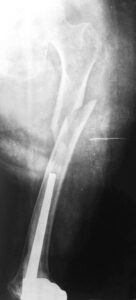

- Περιπροθετικό κάταγμα στην περιοχή στο πέρας του εμφυτεύματος ισχίου σε θήλυ ασθενή .

- Εσωτερική οστεοσύνθεση με πλάκα με αλληλοεπικάλυψη των εμφυτευμάτων για να μην υπάρχουν υψηλές συγκεντρώσεις φορτίων (stress risers)

- H οστεοσύνθεση σε οστεοπορωτικoύς ασθενείς αρχίζει από το γόνατο με σωστή εφαρμογή του εμφυτεύματος και φθάνει μέχρι το ισχίο για να μην υπάρχουν stress risers.